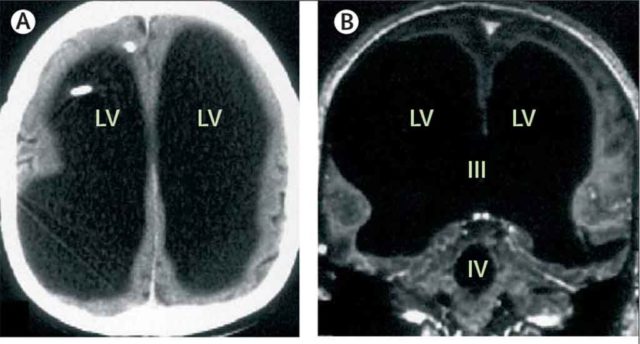

Misteri Pria yang Telah Hidup Normal Tanpa 90% Otak

Apa yang kita ketahui tentang otak tidak seberapa dibandingkan dengan apa yang tidak kita ketahui. Fakta ini dibuat semakin jelas dengan misteri medis seorang ayah dari dua anak asal Prancis berusia 44 tahun yang suatu hari mengetahui bahwa sebagian besar otaknya telah hilang. Sebaliknya, tengkoraknya sebagian besar dipenuhi oleh cairan, hampir tidak ada jaringan otak yang tersisa. Ia memiliki kondisi seumur hidup yang...